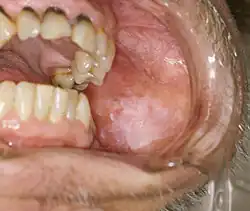

Exophytic leukoplakia on the buccal mucosa

Non-homogeneous leukoplakia is a lesion of non-uniform appearance. The color may be predominantly white or a mixed white and red. The surface texture is irregular compared to homogeneous leukoplakia, and may be flat (papular), nodular or exophytic.[9][15] "Verrucous leukoplakia" (or "verruciform leukoplakia") is a descriptive term used for thick, white, papillary lesions. Verrucous leukoplakias are usually heavily keratinized and are often seen in elderly people. Some verrucous leukoplakias may have an exophytic growth pattern,[2] and some may slowly invade surrounding mucosa, when the term proliferative verrucous leukoplakia may be used. Non-homogeneous leukoplakias have a greater risk of cancerous changes than homogeneous leukoplakias.[9]